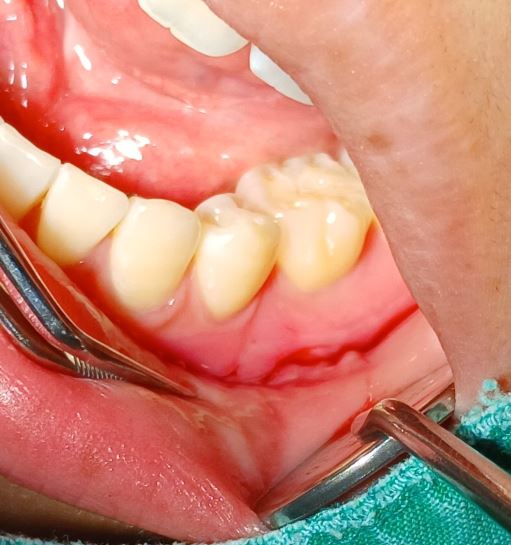

볼 안쪽 섬유종 제거

볼 안쪽 섬유종 제거입니다.

구강외과 전문의가 수술합니다.